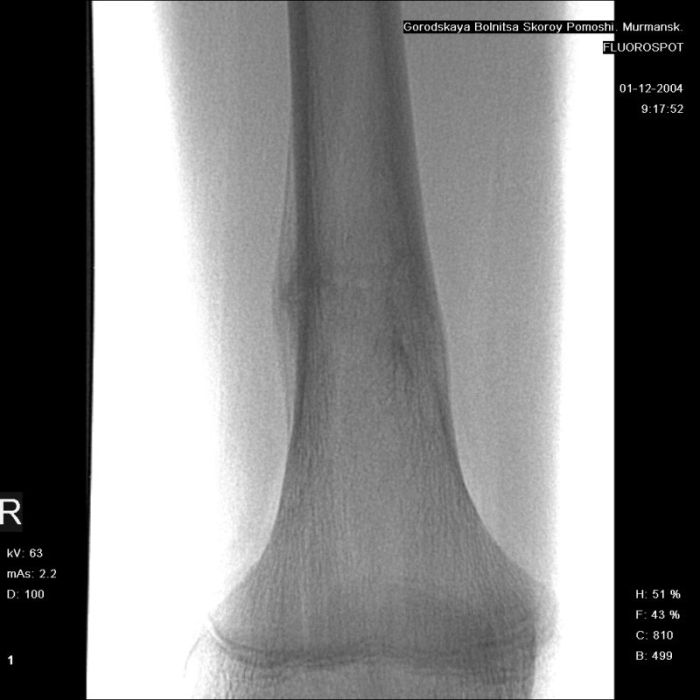

Здравствуйте, уважаемые коллеги!Представляю вашему вниманию интересный случай и пока что непонятный для меня в диагностическом плане. На днях в наше отделение (детской ортопедии и травматологии) поступил 13-летний мальчик по направлению из поликлиники с диагнозом: остеома нижней трети правого бедра.

Анамнез практически никакой: в следствие травмы (растяжение связок коленного сустава) от 07.11.2004 выполнены Rg-граммы в травмпункте и обнаружено опухолевидное образование. Первичные Rg-граммы я не публикую, так как они заметно худшего качества, да и динамики за прошедшие три недели не отражают. Болевой синдром купирован в течение трёх дней. В настоящий момент мальчика ничего не беспокоит. Ходьба не нарушена, опухоль пальпируется с трудом по задней поверхности в н\3 правого бедра, пальпация безболезненна, объем движений в суставах правой нижней конечности полный и симметричный. Кожа над опухолью не изменена.В нашей клинике проведено дополнительное обследование: общие анализы крови и мочи, биохимия крови без особенностей. Выполнены Rg-граммы на цифровом Siemens обычные и продольные томограммы срезами 3-5 мм, а также компьютерная томография поперечными срезами по 5 мм. Прошу обратить внимание, что на приведённых томограммах видны две полости 10х15 мм и 15х60 мм. Также имеются два опухолевидных образований наслаивающихся друг на друга: уплощённое и вытянутое 10х100 мм и элипсовидной формы 15х30 мм. Это хорошо заметно на фото a_1.jpg c_1.jpg и d_1.jpg. Плотность внутри полостей 125% от плотности костномозгового канала, плотность наружного опухолевидного образования 55% от плотности кортикального слоя. Также отмечается линия перелома по центру наружного опухолевидного образования.Исходя из полученных данных мнения в плане диагноза несколько разделились от 1)сочетания кортикальной фиброзной дисплазии и латентно протекавшего маршевого перелома н\3 правого бедра до 2)остеосаркомы. В отношении первого варианта не сходится отсутствие клиники при переломе такой крупной кости как бедро, второй вариант вообще оставлю без комментария, ибо некомпетентен. Хотелось бы услышать мнения коллег, с удовольствием ознакомлюсь с любыми предположениями и замечаниями.С уважением, Александр Е. КлоковОтделение детской ортопедии и травматологииБСМП г. Мурманска.

Думаю, что в этом случае можно думать и об остеоид-остеоме - достаточно чёткие края, более диафизарная локализация, наличие так называемого "гнезда" опухоли, и секвестра, а также отсутствие игольчатого периостита, козырька Кодмана, пятнистостого остеопороза, прорастания в костномозговой канал т.е. признаков остеогенной саркомы.